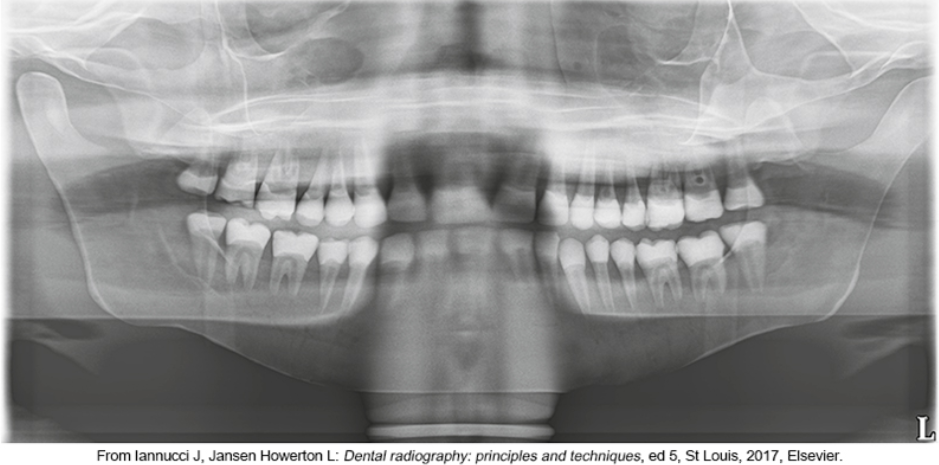

whats the problem

lips arent closed and tongue isnt on palate